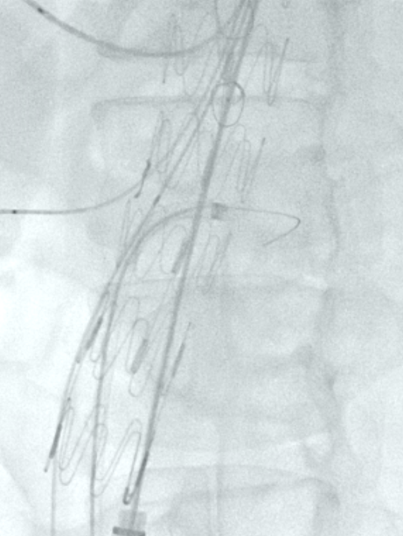

手术步骤:分支超选、导丝到位、解除束径和小支架植入,最终释放主体并桥接远端。

覆膜大支架:选用Ankura II 。

覆膜小支架:使用SilverFlow、VBX、VB等,用于内脏分支重建。

鞘:选用Gore Dryseal和先健Fustar,提供保护和引导作用。

导丝:使用Supracore,提高导丝操作的稳定性和准确性。

穿刺器械:采用先健Futhrough,便于精准穿刺和操作。

手术方案:内脏区体外三开窗(CA、SMA、LRA),RRA原位开窗。

预三开窗+右肾原位开窗重建

Fustar+Futhrough原位穿刺破膜

预三开窗+肾动脉原位开窗重建